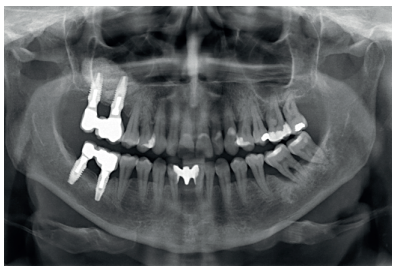

Therefore, it was decided to carry out a sinus lift using biomaterial (bovine hydroxyapatite) bound to PRGFEndoret. The elevation was performed and after five months a new dental cone beam displayed the quantity and quality of the graft obtained for the insertion of dental implants. In the cuts corresponding to the molars of the first quadrant, we observed excellent consolidation of the graft with space to insert 13 mm implants. Today, we would not choose this implant length, since studies published by our group with short and extra-short implants support their use, in addition to showing their diameter is more important than the length to distribute the loads of an already integrated implant; where an 8.5 mm length implant would work in the same way as a 13 mm implant of the same diameter18.

Back in 2007, the therapeutic protocol for these cases was very different (Figures 5-7), with short implants without full development – and without studies demonstrating the importance of diameter over implant length – efforts were focused on the search for anchorage by implant length instead of looking for the bicortical (vestibular-lingual) stability that short and wide implants perform. During this time, the failure of molars 46 and 47 also occurred; these were also extracted and replaced with dental implants.

Six months after implant placement, the final prosthesis was made by using a cemented bridge. This prosthetic protocol is also not one we currently use, where tightness, sealing and the use of screw-retained prostheses using an intermediate or transepithelial component prevail. However, at that time, this type of rehabilitation and the conformation of a “bio” emergence profile in the abutments was how these cases were treated (Figure 8)13- 18. The implementation of transepithelial implants in screwretained prostheses opens a new horizon in the prosthesis, changing our working group protocol of towards an improvement in the implant-prosthesis seal, at the same time as prosthetic imbalance is reduced (due to taking the impression directly on the transepithelial and not on the implant connection) and tightness is improved; which reduces the risk of peri-implantitis, among other things19-20.

After 4 years, the second and third quadrant molars began to have excessive mobility and serious periodontal problems, so it was decided to remove them and regenerate the alveoli with PRGF-Endoret. Once the area was regenerated (a month and a half later), a conebeam was performed to evaluate the residual bone volume. It can be seen how there was an uneven bone crest with areas of 3.3 mm in height up to a maximum of 7 mm (Figures 9 and 10). On this occasion, due to the protocol change described above, we opted for the direct insertion of extra-short implants, since the surgical protocols to address this type of situation in 2011 varied substantially, with these implants being a first-line tool for the treatment of this type of atrophy (Figure 11). Two extra-short implants were selected (5.5 mm diameter x 6.5 mm length for tooth 26, and 6 mm diameter x 5.5 mm length for tooth 27).

Six months after the insertion of the extra-short implants, the final prosthesis was inserted; in this case, screwed and with an intermediate (transepithelial) component; just as the lower prosthesis in the third quadrant was made. At this point in time, the philosophy of work using a screwretained prosthesis with a transepithelial and the search for tightness and passive fit were the dominant concerns for implant rehabilitation, and this is still so today (Figure 12).